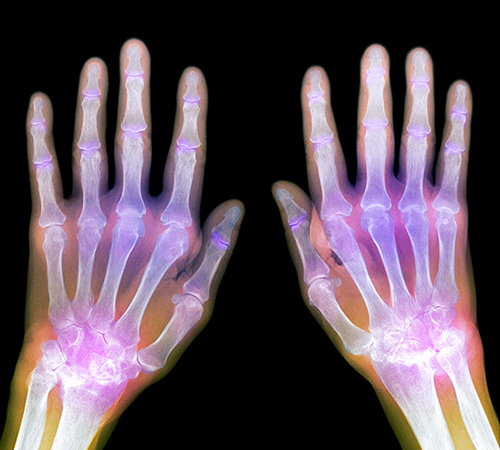

류마티스관절염

• 류마티스관절염

• 류마티스관절염 진단

재 다음 7개의 항목 중 4개 이상을 만족하고 1)~4)의 항목의 증상이

6주 이상 지속될 때 류마티스 관절염 진단을 내리게 된다.

초기 류마티스 관절염은 증상이 애매모호하기 때문에 평균 9개월 정도 진단이 지연되는 경향이 있다.

조조강직: 관절이나 관절 주변의 뻣뻣함이 1시간 이상 지속됨

세 부위 이상에 나타나는 관절염: 의사의 진찰로 3개 이상의 관절에서 동시에 붓기와 삼출이 관찰됨

손 관절의 관절염: 손목, 손가락 중간마디 관절, 손바닥 관절 중 한 관절 이상의 종창

대칭성 관절염: 좌우측의 같은 관절에 증상이 나타남

류마티스 결절: 뼈가 튀어나오거나 관절의 한쪽에 만져지는 피하 결절

혈액검사에서 류마티스 인자 양성

X-선 검사에서 발견되는 뼈의 침식 징후